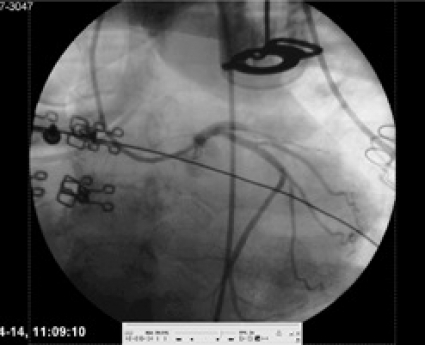

Sinusrytm men kardiogen chock. Patienten var då i kardiogen chock med mycket svaga pulsar spontant. Pulsarna blev åter starka när LUCAS kopplades på igen. Trots dålig prognos beslutades att omedelbart föra patienten till koronarangiolaboratoriet för direkt perkutan koronarintervention (PCI) under pågående LUCAS-behandling. Tre minuter efter ankomst dit punkterades höger a femoralis, kort därefter katetriserades vänster huvudstam. En ocklusion i den främre nedåtstigande grenen (LAD) konstaterades (Figur 1). Tio minuter senare hade ocklusionen dilaterats och stentats till bra resultat (Figur 2). Fullgott flöde (TIMI 3) rådde i kärlet. Patienten fick en reperfusionsarytmi i form av kammarflimmer, som defibrillerades till sinusrytm på första försöket med 200 J. Direkt efter detta var patientens spontana blodtryck ca 60 mm Hg, men efter ytterligare 5 minuter med LUCAS-behandling var det spontana blodtrycket 125/70 mm Hg. LUCAS-behandlingen avslutades.